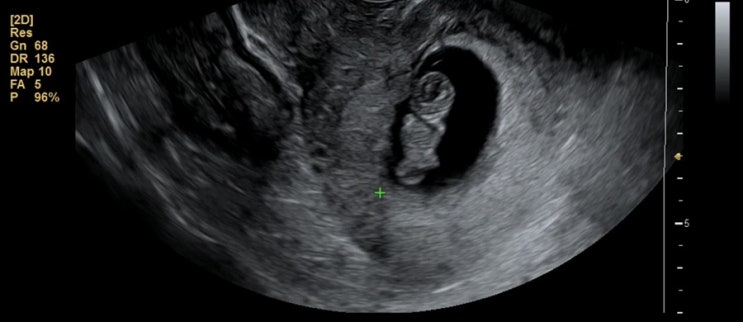

9주1일 젤리곰 행복아 안녕 ?

8~9주쯤 젤리곰 아가를 볼 수 있다. 잔뜩 기대하면서 병원 방문.ㅎㅎ 진짜x1000000000000 너무 귀엽다 ❤️...